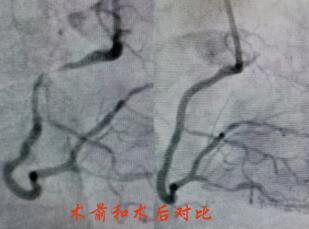

造影提示陶奶奶冠脈病情較重,左主干+三支病變,屬于非常復(fù)雜也極為危險的冠脈病變。經(jīng)過心內(nèi)科介入團(tuán)隊和家屬的反復(fù)溝通,立即對陶奶奶的右冠進(jìn)行了支架置入,術(shù)后陶奶奶的胸痛很快緩解,并經(jīng)過數(shù)天的后續(xù)治療,順利出院。

春節(jié)剛過,陶奶奶的孩子們帶著陶奶奶再次來到了江寧中醫(yī)院心內(nèi)科準(zhǔn)備拆除這顆潛在的“致命炸彈”。韋鋒主任反復(fù)研究陶奶奶的前期手術(shù)影像,心中擬定著多個手術(shù)方案。經(jīng)過充分準(zhǔn)備,2月15日,韋鋒主任再次為陶奶奶進(jìn)行了介入手術(shù)。術(shù)中通過血管內(nèi)超聲(IVUS)精細(xì)、準(zhǔn)確評估陶奶奶的冠脈病變情況,發(fā)現(xiàn)陶奶奶的左主干最小管腔面積僅僅3.7mm2,;前降支近段全程鈣化,最嚴(yán)重處呈270度的環(huán)形鈣化,最小管腔面積僅僅2.1mm2;回旋支開口正常,回旋支近端最小管腔面積1.8mm2。韋鋒主任根據(jù)IVUS的結(jié)果,改變了原來擬定的DKCRUSH術(shù)式,決定采用藥物球囊和藥物涂層支架相結(jié)合的方式處理病變(LCX藥物球囊,LM-LAD植入支架),經(jīng)過近2個小時的手術(shù),陶奶奶的冠脈血管又“完美”地回來了。